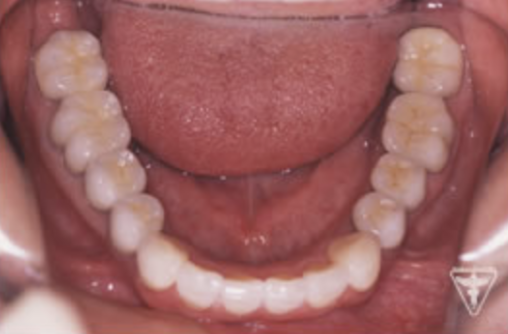

治療前

初診時の正面観・側方観・かみ合わせの面の状態を示します。

下の顎のずれがあるのを確認して下さい。

全顎に補綴処置が施され咬み合せの面がつぶれた様な状態となっている。